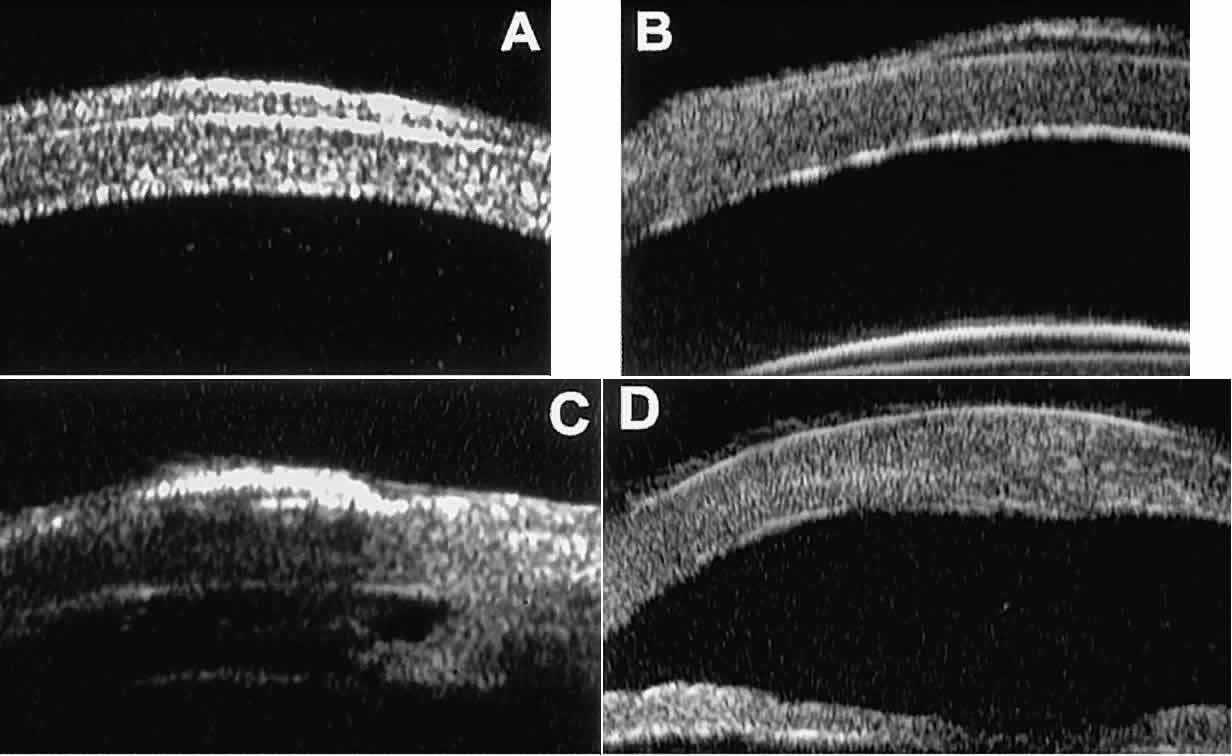

In most patients, the anterior segment can be evaluated thoroughly by slit lamp biomicroscopy unless the cornea is cloudy or opaque. In eyes with a cloudy or opaque cornea, UBM can be used to evaluate the cornea and to define the nature of underlying abnormalities in the angle, iris, ciliary body, lens, and anterior vitreous.4 For example, in eyes with severe congenital malformations of the anterior segment associated with a cloudy or opaque cornea (e.g., Peter's anomaly) (Fig. 14), UBM can be used to define the full extent of the abnormalities and thereby aid the clinician in deciding whether or not to consider any surgical intervention. UBM can also be used to study the extent of some clinically evident corneal abnormalities, such as corneal edema, bullous keratopathy, and band keratopathy (Fig. 15). In eyes with corneal edema (see Fig. 15A), UBM shows the epithelium to be thicker than normal and the stroma to have increased reflectivity. In bullous keratopathy (see Fig. 15B), UBM shows epithelial blisters of the cornea. In band keratopathy (see Fig. 15C), UBM shows superficial calcific deposits that are strongly reflective with shadowing of the underlying structures. In postinflammatory corneal scarring (see Fig. 15D), UBM can show the nonuniform cross-sectional corneal thickness and the presence or absence of a well-defined Descemet's membrane and endothelium layer.

Fig. 14. UBM features of eyes with Peter's anomaly. A. Mild posterior central corneal excavation, absence of Descemet's membrane and endothelium centrally, iridocorneal adhesions to margins of corneal defect, and diffuse hyper-reflectivity of corneal stroma. B. Different patient showing detail of posterior central corneal excavation and diffuse hyper-reflectivity of corneal stroma.

Fig. 15. UBM features of miscellaneous corneal disorders. A. Corneal edema appears as thickening of superficial layer of cornea; corneal stroma is thinner than normal and abnormally bright. B. Bullous keratopathy appears as localized separation of corneal epithelium from Bowman's membrane filled with clear serous fluid. C. Band keratopathy appears as dense, brightly reflective subepithelial plaque in peripheral cornea. D. Postinflammatory corneal scarring after keratitis; note nonuniform corneal thickness and abnormal reflectivity of corneal stroma.

Ultrasound biomicroscopy has also been used to evaluate several anterior scleral disorders,11 including nodular anterior scleritis and scleral hyaline plaques (Fig. 16). On UBM, nodular anterior scleritis (see Fig. 16A) appears as a localized thickening and altered reflectivity of the inflamed sclera. In diffuse non-necrotizing anterior scleritis (see Fig. 16B), UBM shows generalized pronounced thickening of the sclera in the region of involvement. In contrast, after a bout of necrotizing anterior scleritis, UBM can show thinning of the damaged sclera (see Fig. 16C). In eyes with one or more scleral hyaline plaques (see Fig. 16D), UBM shows the lesion to be a highly sonoreflective plate located just anterior to the insertion of the medial or lateral rectus muscle; the lesion has well-defined margins and is so sonoreflective that it shadows the underlying layers of the eye wall.

Fig. 16. UBM features of anterior scleral disorders. A. Nodular anterior scleritis appears as fusiform thickening of limbal sclera. Note apparent lamellae of heterogeneous reflectivity within region of thickening. B. Diffuse anterior scleritis appears as nonfocal scleral thickening in region of inflammation. C. Scleral thinning subsequent to necrotizing anterior scleritis. Note underlying vitreous cells. D. Scleral hyaline plaque appears as dense, hyper-reflective plate several millimeters from horizontal limbus; dense lesion “shadows” deeper tissues.